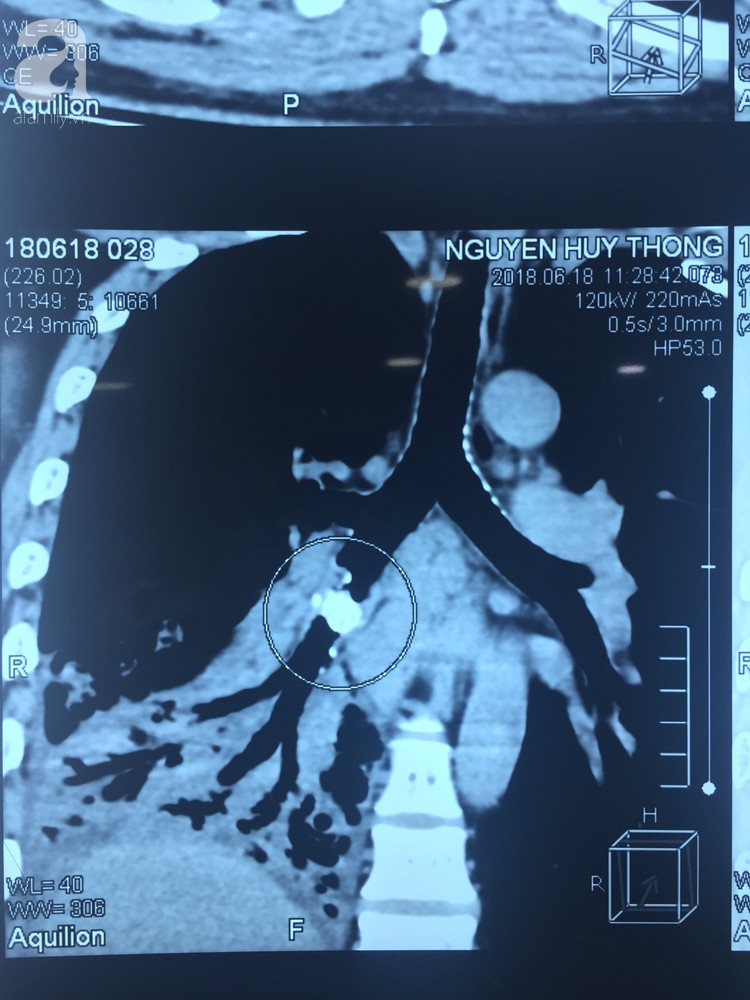

Sau khi thăm khám, ekip điều trị chẩn đoán anh bị viêm phổi. Tiến hành chụp CT phổi, các bác sĩ phát hiện một dị vật nằm trong phế quản của thùy dưới phổi phải. Đây chính là nguyên nhân gây ra các biến chứng viêm phổi cho bệnh nhân.

Ảnh chụp dị vật là chiếc xương cá trong phế quản bệnh nhân.